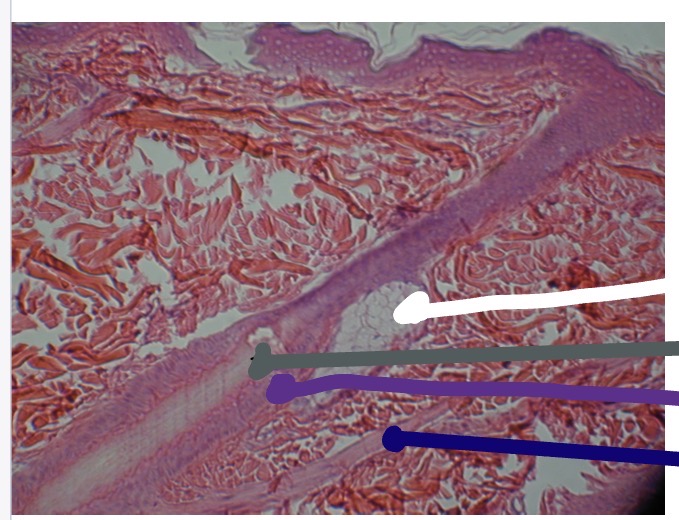

<p>What the orange line in this photo</p>

What the orange line in this photo

Hair root

<p>What’s the dark blue line in this photo</p>

What’s the dark blue line in this photo

Hair follicle

<p>What’s the blue line in this photo</p>

What’s the blue line in this photo

Sebaceous gland

<p>What is the white line in this photo</p>

What is the white line in this photo

<p>What is the grey line in this photo</p>

What is the grey line in this photo

<p>What is the purple line in the photo</p>

What is the purple line in the photo

<p>What is the dark blue line in this photo</p>

What is the dark blue line in this photo

Arrector Pili muscle